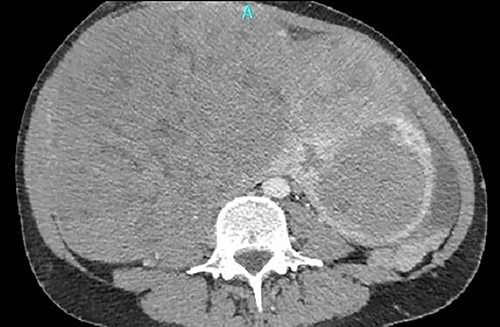

A single 46-year-old woman had a known history of huge uterine fibroids growing for the last 12 years. In her current presentation, the uterine with the fibroids was extending from the xiphoid to pubis, resulting in a recent common iliac vein thrombosis. The patient underwent a magnetic resonance imaging study of the abdomen, which showed enlarged uterine fibroids; the largest (21 cm in diameter) projected to the right lateral abdomen, compressing the gallbladder and the inferior vena cava (IVC).

One month later, after vascular consultation, a chest and pelvis computed tomography angiography was performed and a huge mass originating from the uterine wall was revealed (26 cm in diameter) (Fig. 1). The mass compressed the surrounding organs, especially IVC (Fig. 2). Furthermore, thrombosis of left femoral and external and common iliac veins, as well as infrarenal IVC patency (without clarification of IVC thrombosis), was detected. The common, internal and external right iliac veins were patent, and no PE was detected.

A huge mass originating from the uterine wall was revealed after pelvis CTA.